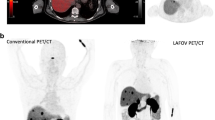

In common with most centres, our SAFOV imaging protocol captures the skull base to the mid-thigh, where restriction of the examination volume allows the scan to be completed faster. One advantage of the uExplorer is the ability to capture the entirety of the human organism from head to toe; other LAFOV systems can capture the head and torso in a single FOV. This ability to image the entire torso represents a significant advantage, for example when exploring whole-body organ interactions [38] or to enable whole-body, multi-organ kinetic imaging [39] which potentially reveals insights which previous generation SAFOV could not provide. Figure 1 shows an example of a patient acquired using a dynamic imaging protocol with our LAFOV system and demonstrates the high-temporal resolution and low-noise whole-body dynamic data which can be achieved using LAFOV systems.

Selected time frames for a patient examined at the University Hospital, Bern with breast cancer (top row between 0-60s p.i.; bottom row circa 5 min, 30 min and final static scan at 55–65 min) demonstrate the excellent temporal and spatial resolution offered by LAFOV systems. The radiopharmaceutical (2-[18F]FDG) can be traced through the pulmonary vasculature, arteries and venous system with small to medium sized vessels visible